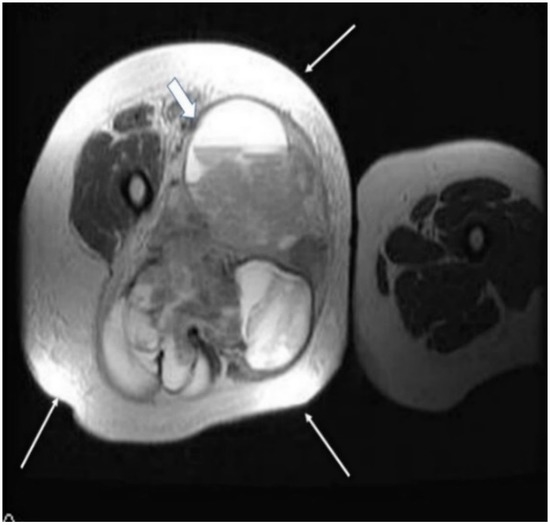

2.2. Imaging Examinations